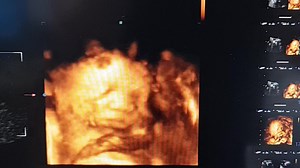

Birth Center Tour